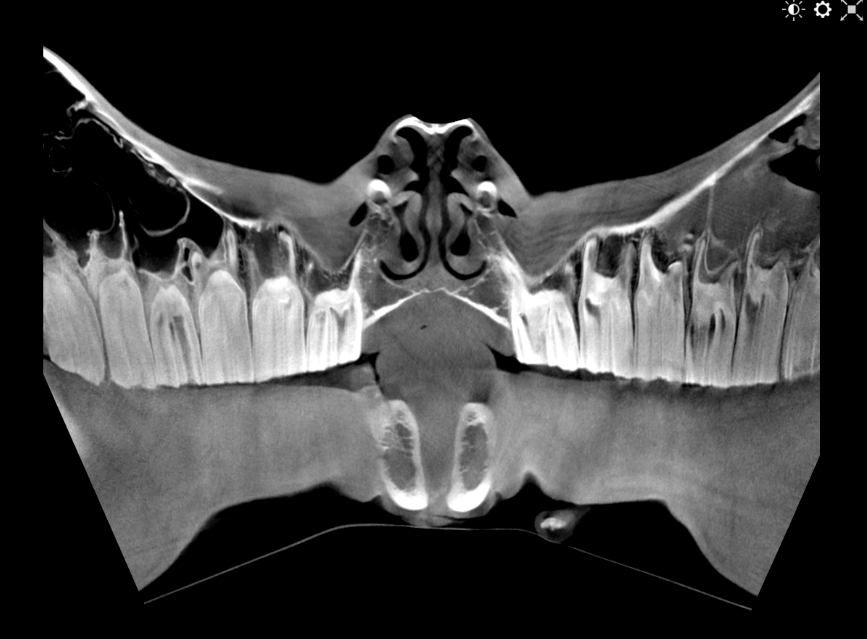

Our High Definition Volumetric Imaging (HDVI) technology represents the most advanced stage of Flat Panel CT technology. It offers exceptional diagnostic imaging for both hard and soft tissues, in diagnostic settings and intraoperative theaters. It is the gold standard for orthopedic applications.

Pegaso enhances safety and usability by enabling the scanning of a standing horse’s head, neck, and limbs.

Scan of the standing horse

Pegaso scans head, neck and limbs of the standing horse

High Definition Volumetric Imaging (HDVI) technology